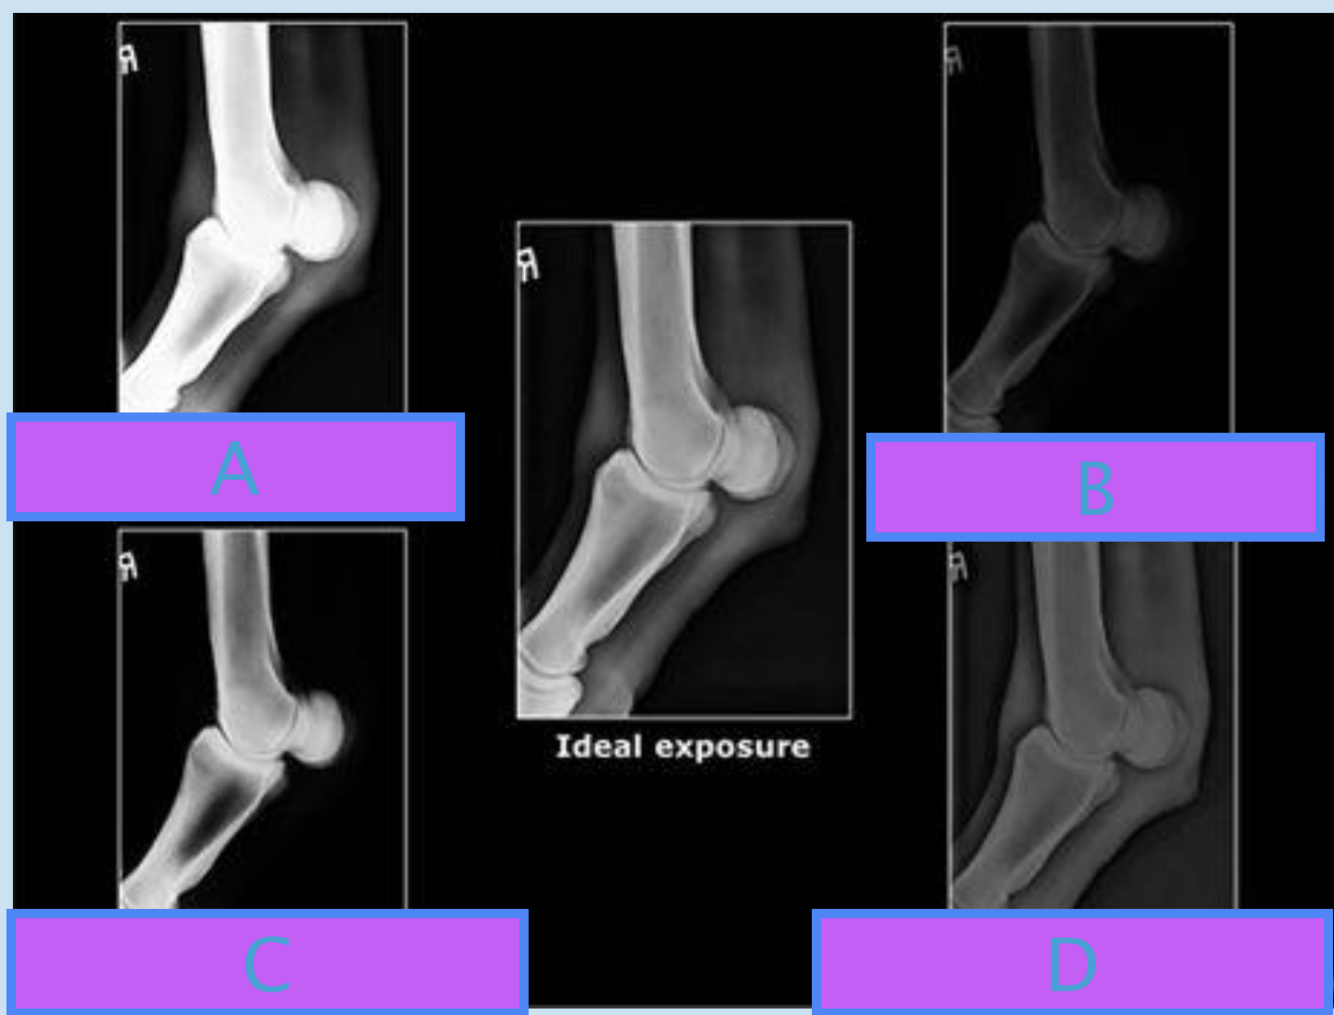

A

A Underexposed - mAs low

B

B Overexposed - mAs high

C

C Increased contrast - kv low

Q

D

D Decreased contrast - kv high